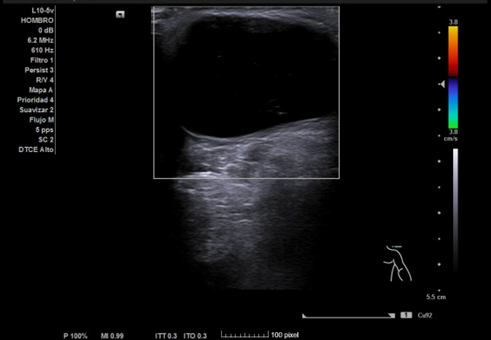

Ecografía hombro izquierdo: se observa una masa de 2,3 x 3,4 cm, anecoica en su totalidad, no tabicada, de bordes bien definidos y sin captación en Doppler.

Diagnóstico final: quiste sinovial probablemente perteneciente a la articulación acromioclavicular.

Diagnósticos diferenciales: Signo del Geyser, Lipoma, Hematoma organizado o seudoquiste.